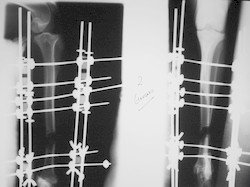

Fijación Externa

Fijación externa en IVOT

PRÁCTICAS CURSO DE FIJACIÓN EXTERNA PERFECCIONAMIENTO.

Elongacion.